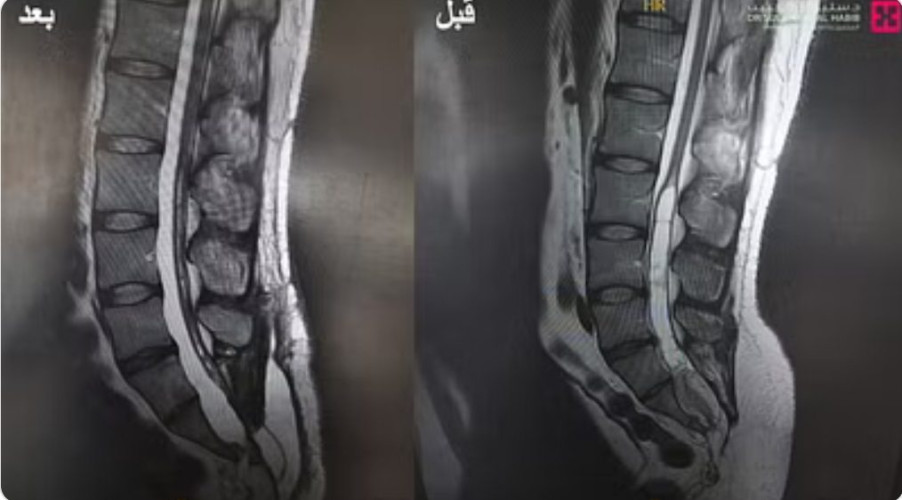

واستطرد د.النبهان، أن الفريق الطبي أخضع المريض لعدة فحوصات دقيقة؛ حيث كشفت صور الرنين المغناطيسي وجود عيب خلقي، وورم كبير مخترق للقناة الشوكية، في أسفل النخاع الشوكي ومربوط أسفل “العظم الحرقفي”، وسبّب ذلك ضغطًا وشدًّا للنخاع إلى الأسفل، بالإضافة إلى توسعه بسبب امتلائه بالسوائل.

وأوضح أن الفريق الطبي بعد الاطلاع على نتائج الفحوصات، أجرى للمريض عملية دقيقة باستخدام المجهر الجراحي “Pentero”، تم فيها استئصال كامل الورم الذي بلغ طوله 15 سم، ومتغلغلًا في القناة الشوكية، ومن ثم تم إغلاق فتق النخاع بخيوط جراحية دقيقة جدًّا “0/8″؛ لكننا واجهنا مشكلة عند ترميم الفجوة التي خلّفها استئصال الورم؛ حيث لم تكن هناك عضلات كافية لتغطيتها، فاستعضنا عنها بغشاء صناعي بحجم “10 × 5 سم”.